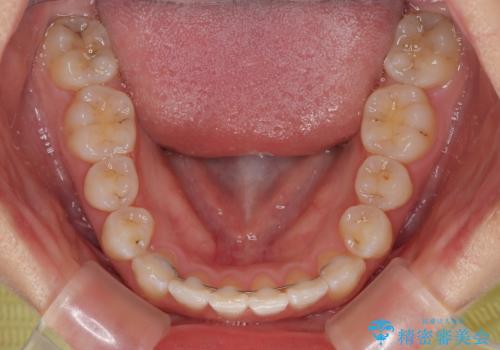

想定通り、1年強で綺麗に仕上げることができました。